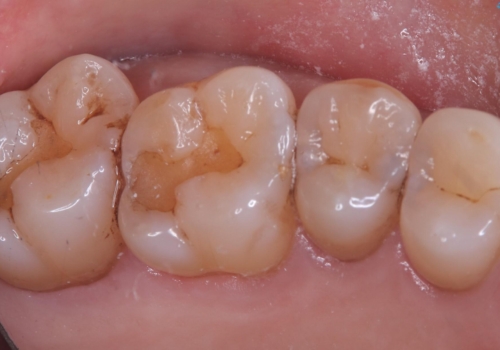

- 主訴:海外に行く前に虫歯があるなら全部しっかり治したい。

右上5番にう蝕があり、審美性・適合性・材料安定性の高いセラミックインレーでのやり替えとなりました。

右上5番の近遠心にう蝕が認められたため、CR裏層の後MOD窩洞のセラミックインレーとしました。